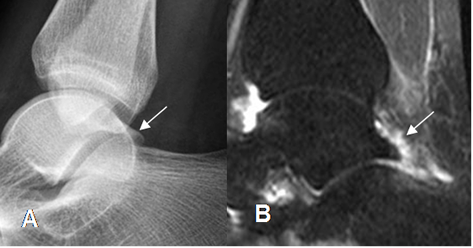

Fig 99. Pinzamiento posterior por proceso de Stieda.

A: Rx lateral y B: TAC reconstrucción sagital. Prominencia en la parte posterior del talo, que comprime los tejidos blandos y corresponde a proceso de Stieda.

C: TAC corta axial. Proceso de Stieda y osteofitos que ocupan el canal del flexor del hallux.